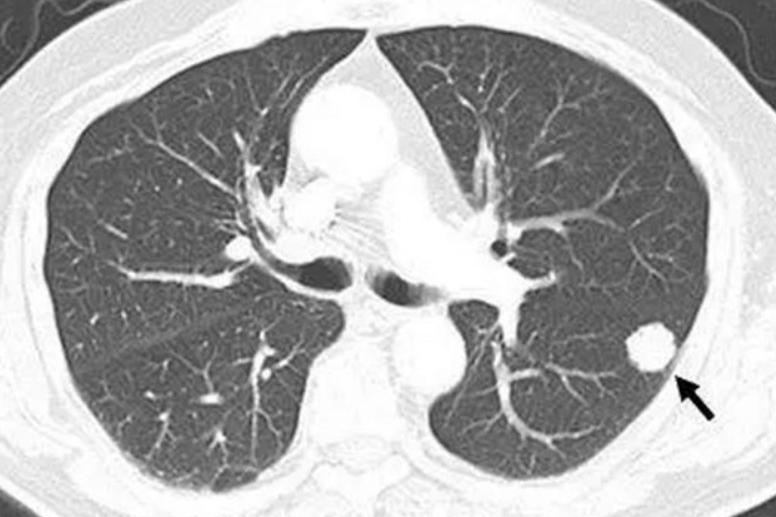

大几万切除的肺结节卷土重来,中医几味常见药铲除病根,无条件分享 “大夫,我花几万块切的肺结节,怎么才半年就又长了?”这是门诊最常听到的一句话。从医40余年,我见过太多肺结节患者,砸几万块做了切除手术,本以为高枕无忧,复查时却发现结节卷土重来;更有甚者术后怕复发,盲目吃靶向药、补保健品,把脾胃伤得一塌糊涂,结节没防住还添了新病。 其实结节反复,根源从不是“切得不够干净”,而是术后正气没补、痰瘀没化,给了结节再生的土壤。 55岁的张先生就是典型病例:去年因8毫米肺结节手术切除,术后花两万多吃靶向药“巩固”,半年后复查左肺又现5毫米结节,还伴胸闷、恶心、乏力,经人介绍前来求诊。 我观其舌苔白厚腻、舌质淡暗,脉细弱,结合手术耗气、药物伤脾的病史,精准辨证为“肺脾两虚、痰瘀内阻”。术后正气耗伤又受药物损伤,导致痰湿不化、气血运行不畅,才会反复生结节并出现乏力、恶心等症状。 于是开方: 柴胡、郁金、当归、白芍、白术、茯苓、浙贝母、生牡蛎、夏枯草、瓜蒌、黄芪、党参、炙甘草。 并嘱咐每日慢走20分钟,清淡饮食、规律作息。 仅28天复诊,张先生胸闷、恶心感全消,可正常散步40分钟,CT显示结节边界清晰无增大; 调整药方巩固两疗程后,结节缩小至3毫米,各项指标稳定。 我根据他的恢复情况调整了药方,让他再服两个疗程巩固。 上周他来复查,精神头明显好了很多,CT显示左肺结节缩小到3毫米,胸闷、乏力等症状完全消失,体重也恢复到了术前水平,各项指标都很稳定,整个人的状态跟之前大不相同,吃饭正常,脸色泛红晕,心情舒畅,也不失眠焦虑了。 中医调理,就是补正气、化痰瘀,从根上断结节再生之路。这张方子的精妙之处,在于“标本兼顾、攻补兼施”,每味药都直击病机: 柴胡、郁金——疏肝解郁、行气止痛,打开郁结的气机,从根源上减少痰瘀生成,改善胸闷和情绪问题; 当归、白芍——养血活血、柔肝缓急,辅助疏肝理气,同时改善因气滞血瘀导致的胸痛、月经不调; 白术、茯苓——健脾益气、燥湿化痰,增强脾的运化功能,减少痰湿生成,从源头切断结节“养料”; 浙贝母、生牡蛎、夏枯草——软坚散结、清热化痰,直击肺内结节,逐步化解凝结的痰瘀; 瓜蒌——清热化痰、宽胸散结,既能化解肺内痰湿,又能缓解胸口憋闷疼痛; 黄芪、党参——补气健脾、益肺固表,补充肺脾之气,提高机体运化和代谢能力,防止结节复发; 炙甘草——调和诸药,同时益气和中,辅助脾胃运化。 我是中医何延忠,从医40余年,我始终坚信,结节的形成与个人体质、生活习惯密切相关,“辨证施治、一人一方”的个性化调理,才是解决结节问题的根本之道! 中医结节肺肺结节[超话]